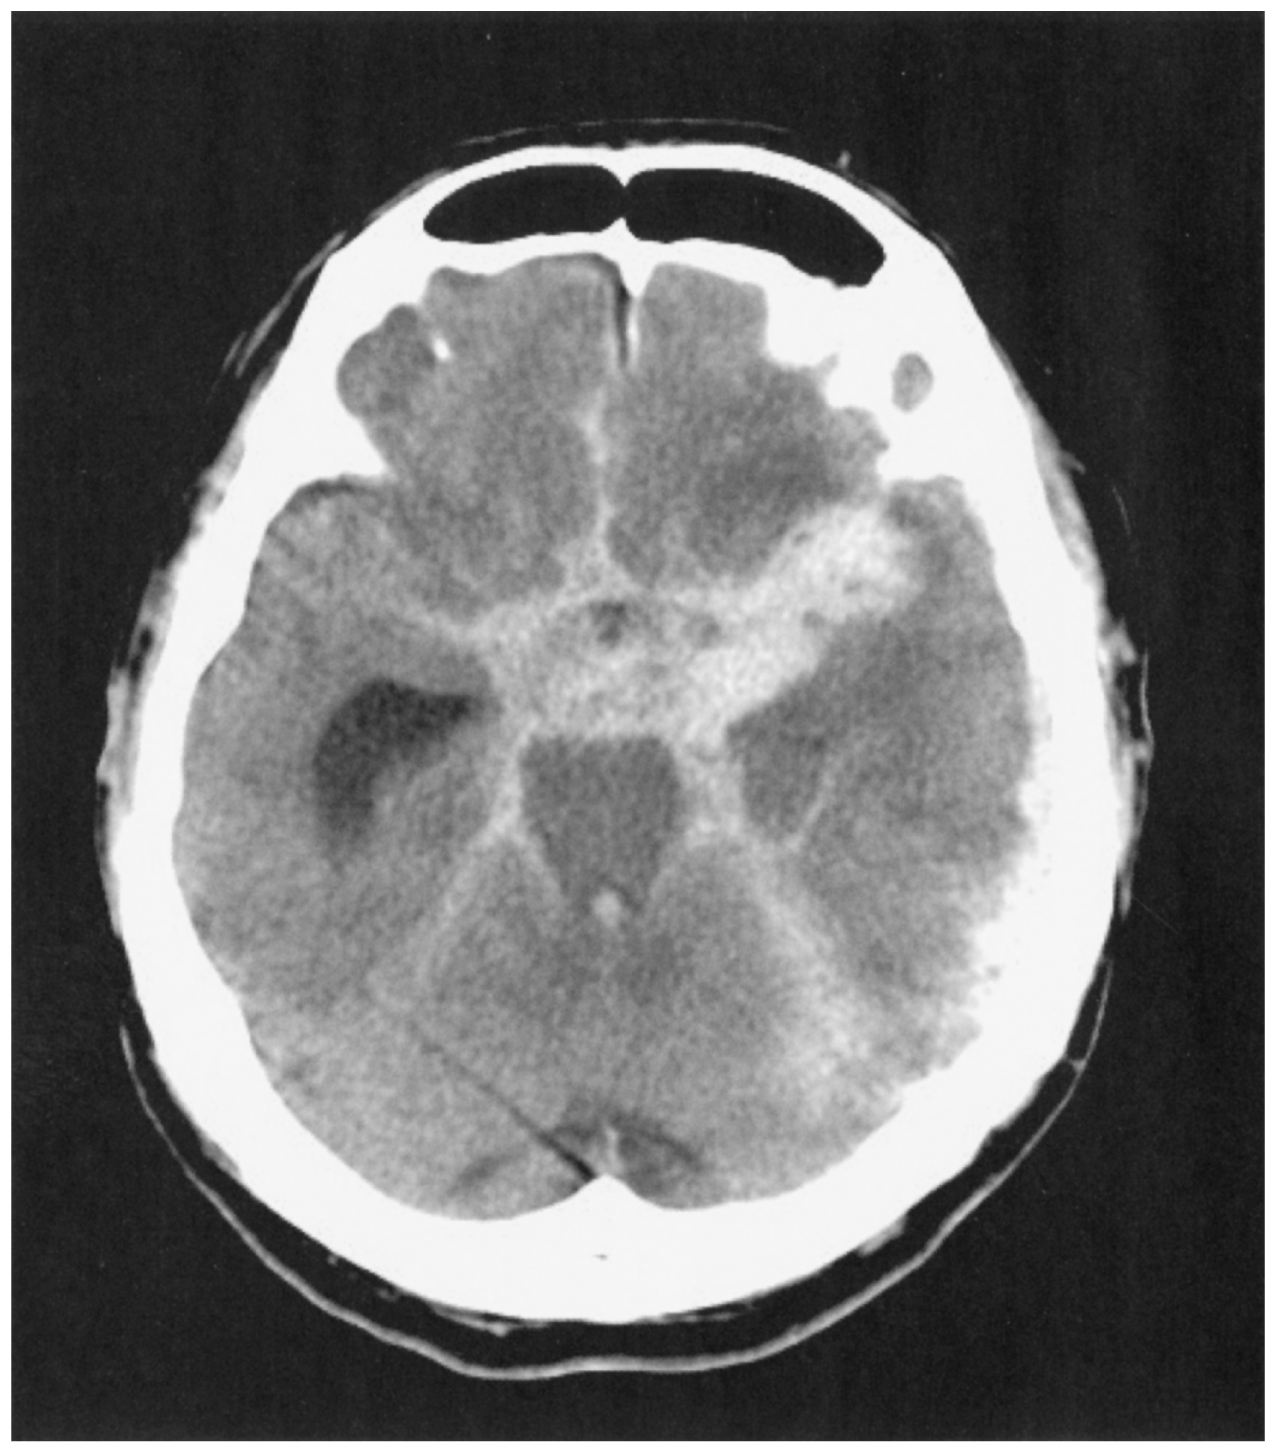

57歳の男性。突然生じた激しい頭痛を主訴に救急車で搬入された。数日前から軽度の頭痛と複視,軽度の左眼瞼下垂を認めていた。既往歴に特記すべきことはない。頭部単純CTを下に示す。

破裂脳動脈瘤の部位として最も可能性が高いのはどれか。